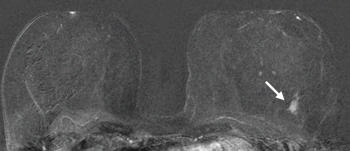

Figure 1. Images in a 55-year-old screening participant. (a, b) Normal digital full-field mediolateral oblique (a) and craniocaudal (b) mammograms (BI-RADS category 1) show a heterogeneously dense breast (ACR category C). (c) Screening ultrasound image shows normal findings (BI-RADS category 1). (d) MR-guided biopsy enabled us to confirm the presence of an invasive high-grade triple-negative cancer (no special type [NST], pT1b, N0, M0). (d) Breast MR image shows a suspicious enhancing mass (arrow) in the left breast (BI-RADS category 5).E

Figure 6. MR-guided biopsy enabled us to confirm the presence of an invasive high-grade triple-negative cancer. Breast MR image shows a suspicious enhancing mass (arrow) in the left breast (BI-RADS category 5).